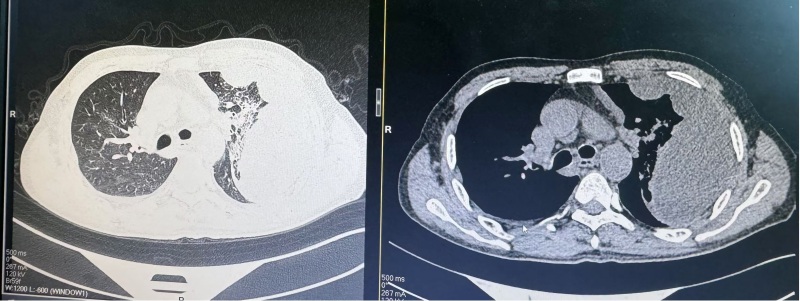

News患者苏先生,今年49岁,因“咳嗽、咳痰伴发热10天”就诊于我院呼吸与危重症医学科一病区,入院后完善胸部CT提示:两肺炎症改变,右肺多发结节,两侧胸腔积液,左肺病变伴包裹性胸腔积液合并肺膨胀不全。患者在胸水NGS、胸水脱落细胞病理检查后仍不能确定左肺病变性质,科室团队进行集体讨论之后拟行胸腔镜检查进一步明确诊断。在与患者及家属沟通后,决定实施内科胸腔镜手术。